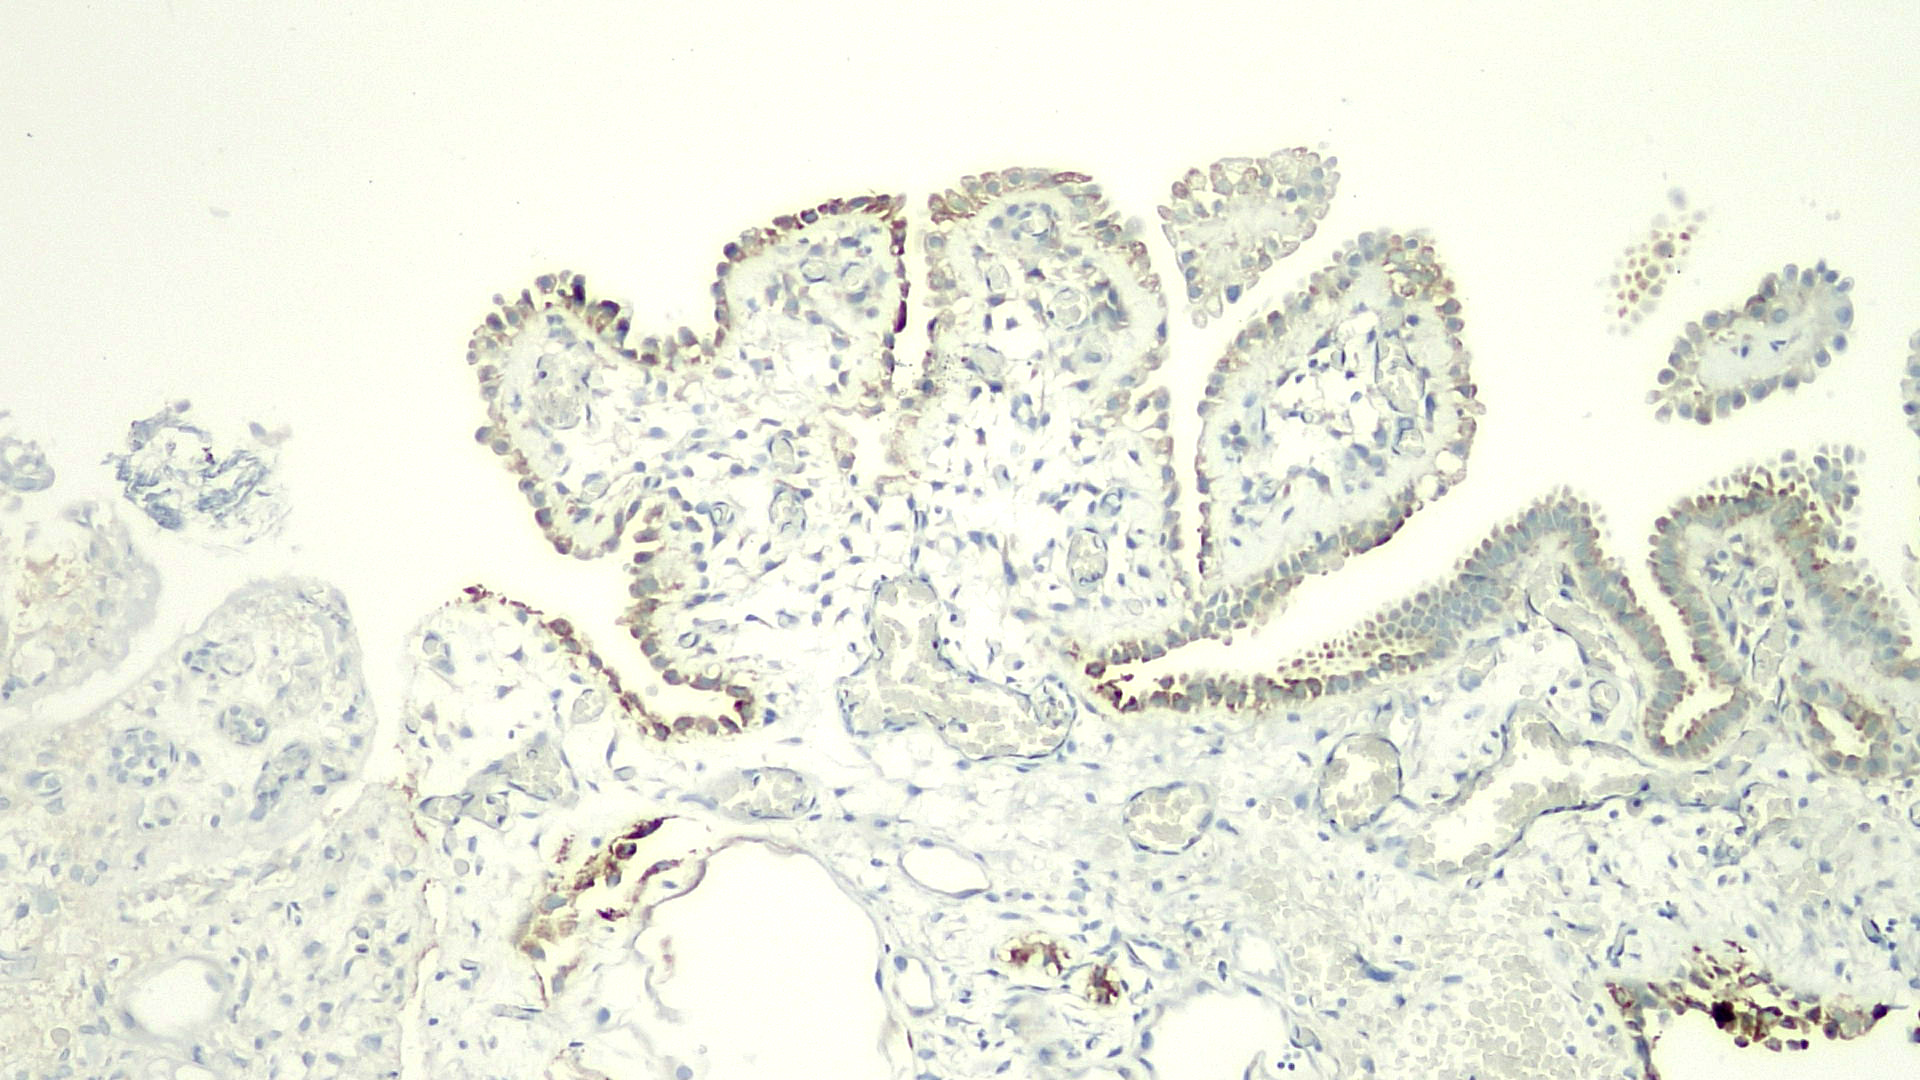

Microscopic (histologic) images

Positive stains

- PAX2, PAX8, AMACR, CD10, CK7 (Am J Surg Pathol 2014;38:1664)

- CK903, EMA, S100A1 (Ann Diagn Pathol 2013;17:41)

- Napsin A (Hum Pathol 2020;102:23)

- Weakly positive or negative for PSA and PSAP